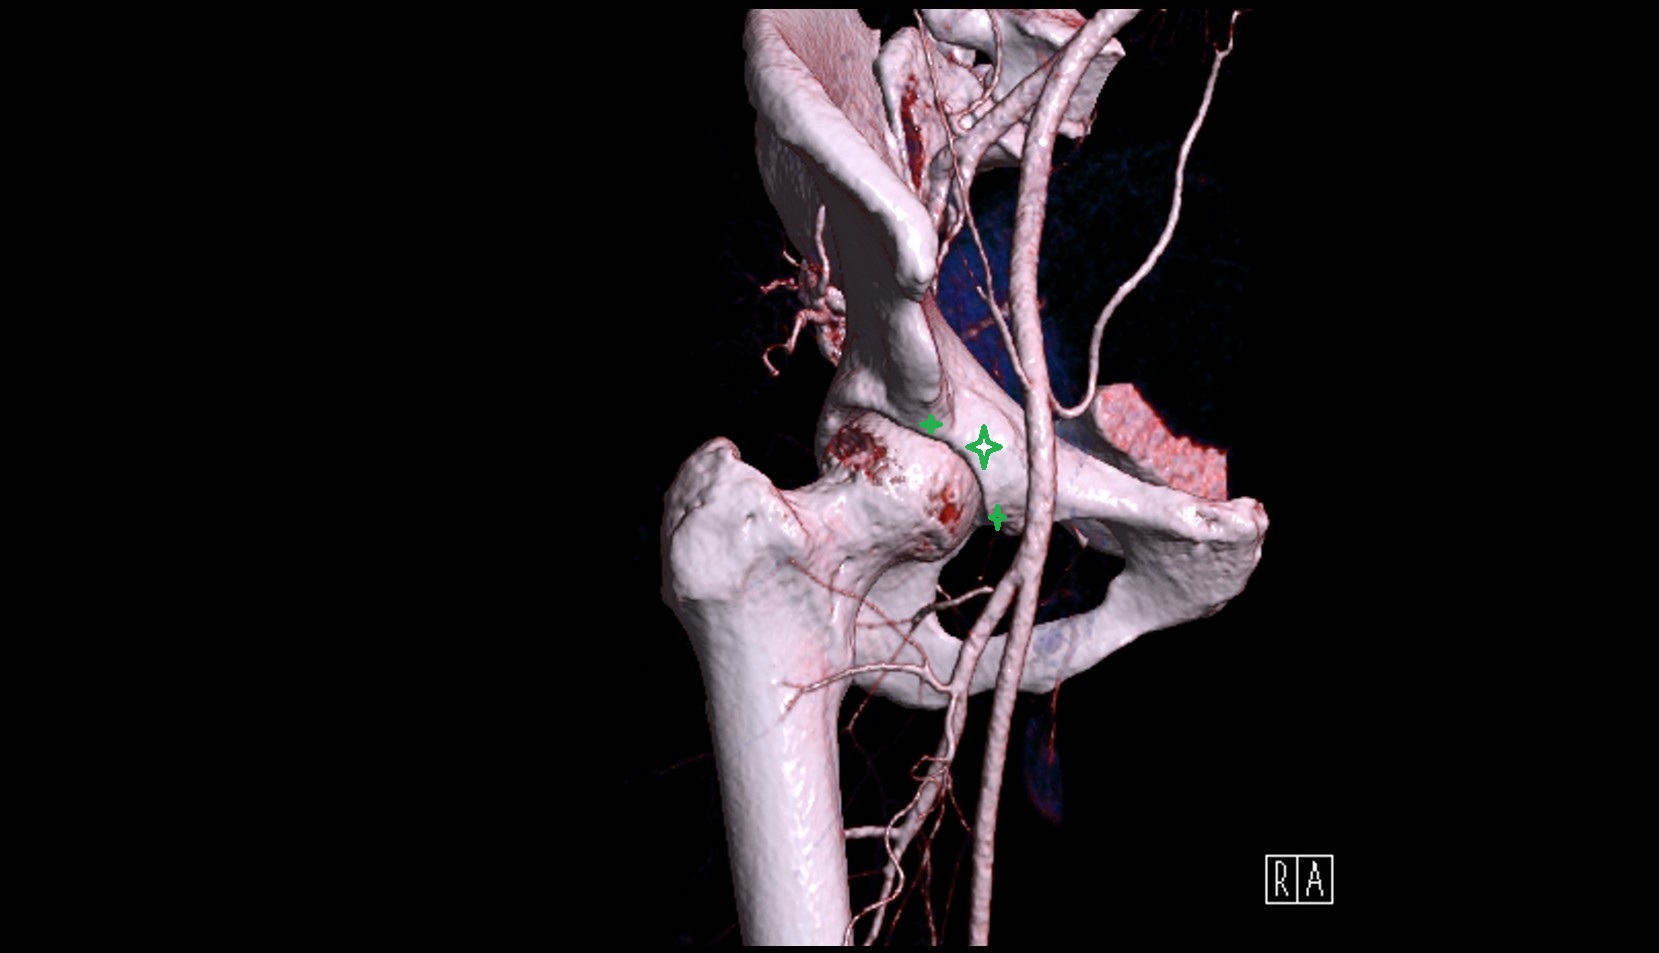

- Femoral artery

- External iliac artery

- Internal iliac artery

- Deep femoral artery (profunda femoris)

- Medial circumflex femoral artery

- Lateral circumflex femoral artery